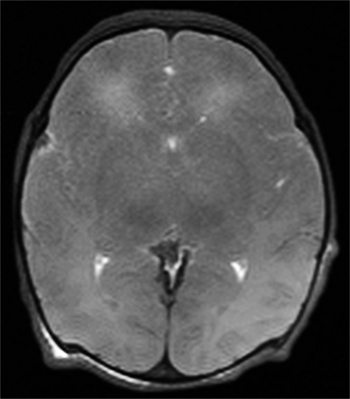

Multiple cerebral ischemic events may lead to subcortical ischemic depression, also known as vascular depression. This condition is most commonly seen in elderly depressed patients.[citation needed] Late onset depression is increasingly seen as a distinct sub-type of depression, and can be detected with an MRI.[11]